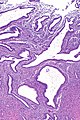

Micrograph showing endometrium with changes due to a SPRM. H&E stain. | |

| LM | glandular changes - extensive cystic dilatation, inactive appearing glandular epithelium or abortive subnuclear vacuolization, rare mitoses or apoptotic cells, abnormal stromal vessels (common) |

| LM DDx | endometrial hyperplasia |

- Glandular changes - extensive cystic dilatation.

- Inactive appearing glandular epithelium or abortive subnuclear vacuolization.

- Rare mitoses and apoptosis.

- Abnormal stromal vessels - common.